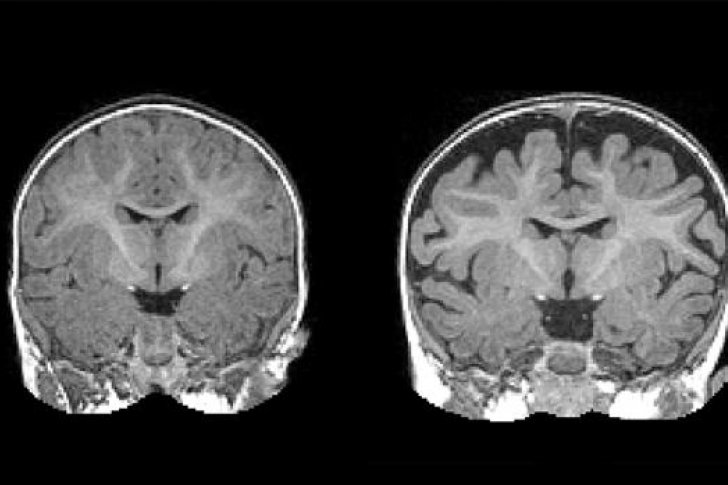

Así, el nuevo estudio tuvo por objetivo evaluar la posible asociación entre el líquido cefalorraquídeo podría servir como biomarcador de un incremento del riesgo de desarrollo de TEA. Y para ello, los autores realizaron pruebas de resonancia magnética a 343 bebés cuando contaban una edad de seis, 12 y 24 meses. Hasta 221 de los bebés contaban con hermanos mayores diagnosticados de TEA, o lo que es lo mismo, tenían un riesgo elevado de autismo. No así los 122 restantes, cuyas familias no tenían ningún miembro diagnosticado del trastorno.

Los resultados mostraron que, comparados con aquellos que no llegaron a padecer el trastorno, los bebés que acabaron desarrollando un TEA tenían una cantidad de líquido cefalorraquídeo significativamente mayor en el espacio subaracnoideo a la edad de seis meses. De hecho, y por lo que respecta a los bebés que fueron ulteriormente diagnosticados del trastorno, la cantidad de líquido en este espacio cercano al perímetro del cerebro fue hasta un 18% mayor. Tal es así que la detección de este mayor contenido de líquido cefalorraquídeo es capaz de predecir qué niños acabarán desarrollando autismo con una precisión del 70%.

Es más; como apunta Mark Shen, «cuanto mayor fue la cantidad de líquido cefalorraquídeo en el espacio extraaxial a los seis meses, más severos fueron los síntomas del TEA cuando el niño fue diagnosticado de autismo a los 24 meses de edad».